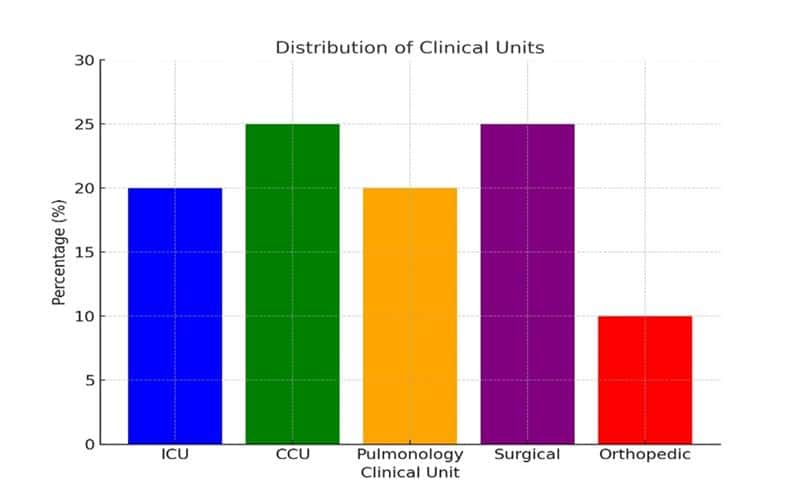

Knowledge and Practices of the Nurses Regarding Central Line Associated Infection at Tertiary Care Hospital, Peshawar, Pakistan

Background: Central Line-Associated Bloodstream Infections (CLABSIs) are a considerable source of increased mortality and morbidity during intensive care unit stays....Read More